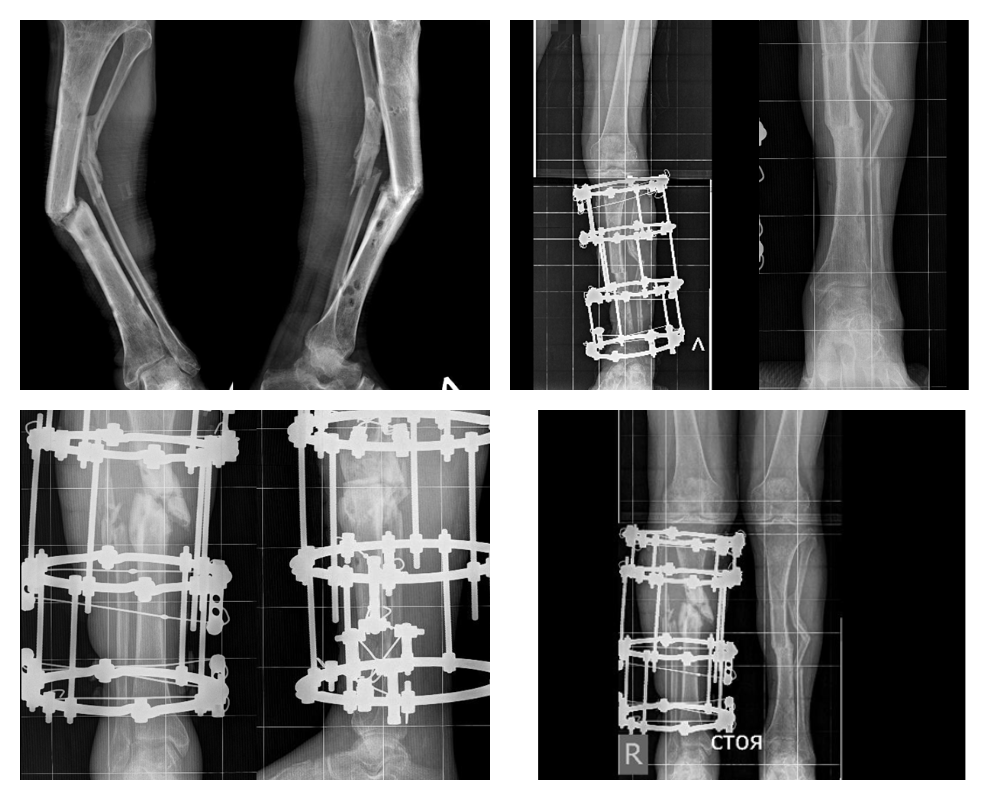

56-летний пациент из Биробиджана получил в дорожной аварии серьезную политравму обеих нижних конечностей. Лечение по месту жительства в 2023 году было связано с первичной хирургической обработкой ран и остеосинтезом голеней аппаратом Илизарова.

Однако лечение не принесло ожидаемых результатов, сращения переломов достичь не удалось. Постепенно сформировалась выраженная деформация обеих голеней более 45 градусов.

- Первым этапом мы по методу Илизарова исправили деформацию левой голени, достигли консолидации отломков в правильном положении. Вторым этапом уже в этом году выполнили корригирующую остеотомию костей правой голени и остеосинтез аппаратом Илизарова. Мы очень довольны результатом.

Восстановлена биомеханическая ось обеих нижних конечностей, пациент на период фиксации поехал домой, выполняя рекомендации врачей Центра Илизарова под наблюдением местных специалистов, - рассказал заведующий отделением №3 Центра Илизарова, к.м.н. Виталий Нарицын.